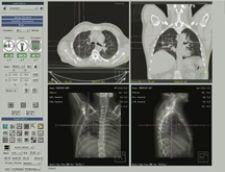

Philips’ exclusive Tumor Localization (Tumor LOC) application allows radiation oncology departments to localize target volumes for radiation therapy planning.

Designed for fast and simple CT tumor volume localization, the application includes exclusive features for viewing Respiratory Correlated CT datasets and analyzing motion of the target and surrounding anatomy.

Previously only available on the Philips Brilliance CT Big Bore console, version 3.5 makes the Tumor LOC application available for purchase on the Extended Brilliance Workspace (EBW) and GEMINI TF PET/CT systems.

All of the best-in-class 4D tools found on the console will now be available on the EBW, reportedly enhancing workflow efficiency and flexibility in the radiotherapy department.